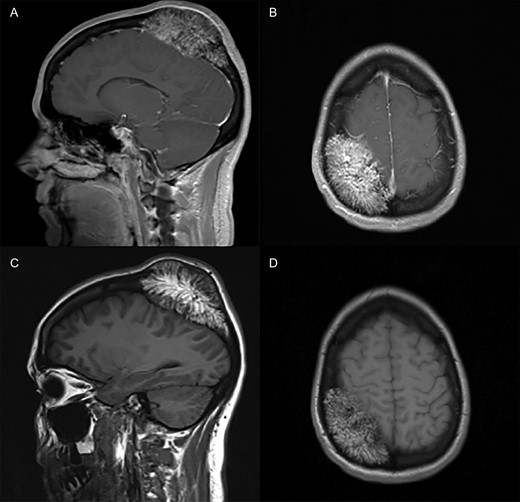

CT scans showed a 6.4 cm × 6.4 cm × 4 cm right parietal calvarial mass (Fig. 1) with expansion of the diploic space and mass effect on the right parietal lobe.

CT bone window with sagittal (A) and axial (B) views provided. A large right parietal calvarial mass expanding into the diploic space and exerting mass effect on the right parietal lobe is demonstrated.